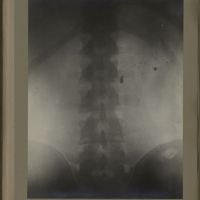

0118 - Page 6 - [Radiographie du rachis lombaire]0118 - Page 6 - [Radiographie du rachis lombaire]

0133 - Page 21 - [Radiographie du rachis lombaire]0133 - Page 21 - [Radiographie du rachis lombaire]

0136 - Page 24 - [Radiographie du rachis lombaire]0136 - Page 24 - [Radiographie du rachis lombaire]